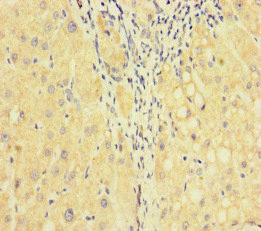

Rabbit Polyclonal Factor V antibody - conjugated to Biotin. Suitable for ELISA and reacts with Human samples. Cited in 1 publication. Immunogen corresponding to Native Full Length Protein corresponding to Human F5.

Factor V also known as proaccelerin is a coagulation factor playing a main role in blood clotting. This protein with a molecular mass of approximately 330 kDa is synthesized in the liver and found in plasma. The Factor V protein is essential for the coagulation cascade functioning as a pivotal mediator in the conversion of prothrombin to thrombin. It exists in plasma in an inactive form until activated by thrombin or factor Xa to fulfill its mechanical function in hemostasis.

The mechanism of Factor V involves its function as a cofactor to Factor Xa in the prothrombinase complex. This complex formation enhances the efficiency of thrombin generation considerably accelerating clot formation. Factor V once converted to its active form aids in forming a stable clot by bridging and immobilizing cellular elements and fibrin strands. Expression occurs mainly in the liver but it also manifests in platelets where it enhances thrombin production during platelet activation and aggregation.